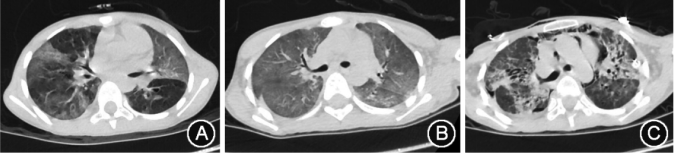

图1 52岁的女性植入综合征

图2 27岁男性IPS患者

图3 IPS患儿肺部HRCT